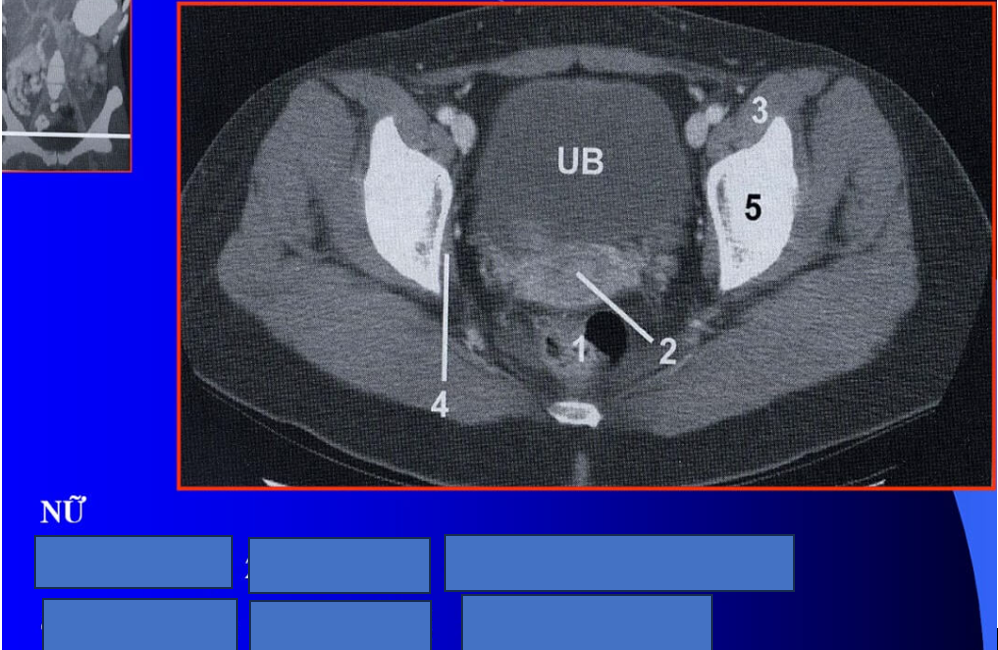

manh tràng? x cùng?